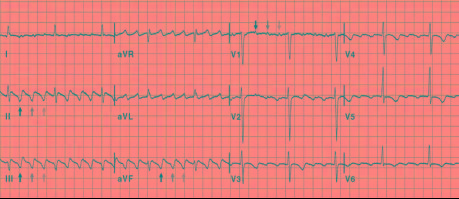

心房扑动(简称房扑)是心房快速而有规律的电活动 , 心房的频率一般为250~350次/分 , 体表心电图上表现为心房扑动波 , 心房波间无明确的等电位线 , 心室频率决定于心房激动下传至心室的比例 , 常见为2:1和4:1房室传导或不等传导 。 房扑患者一般多伴有各种器质性心脏病 。